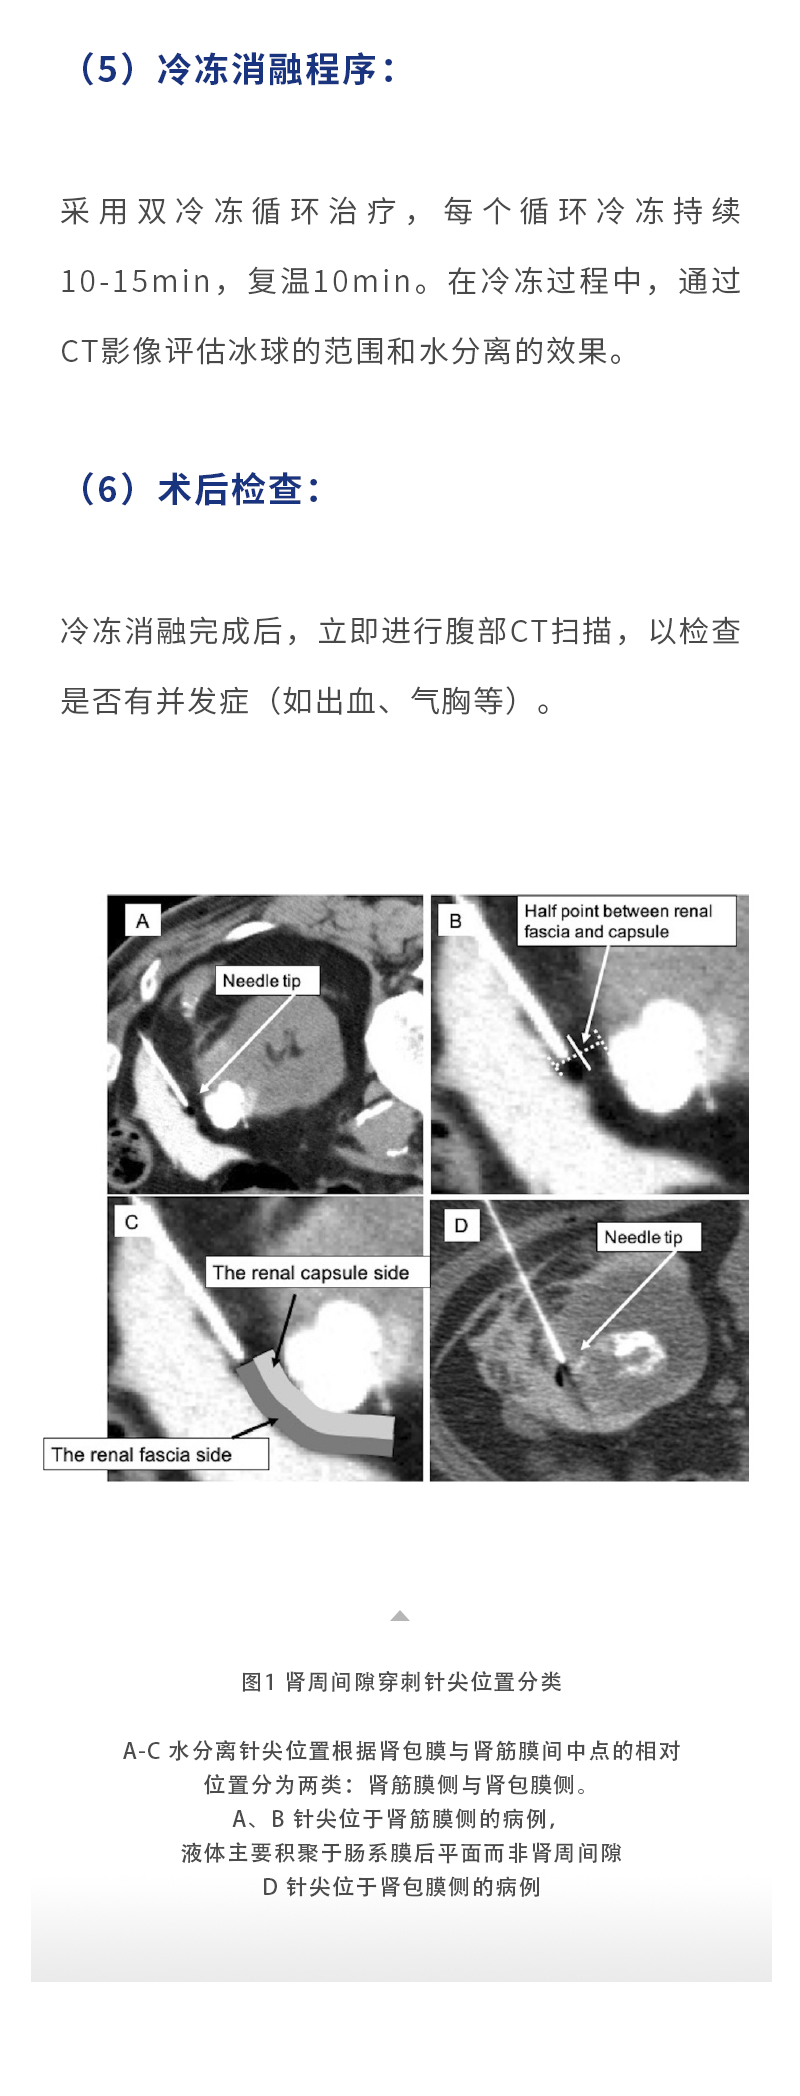

【HYGEA·科研資訊】腎癌冷凍消融